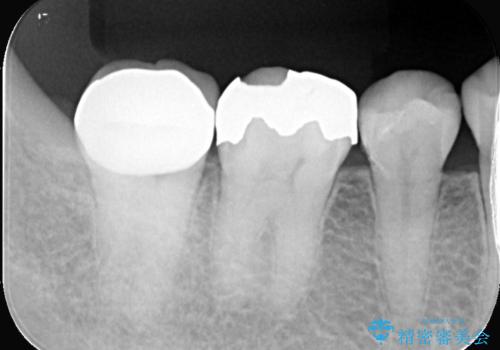

- 銀歯と歯の間に穴があり虫歯になっていました。

銀歯と虫歯を除去後、オールセラミッククラウンで治療を行いました。

銀歯のほとんどは錆びる金属で出来ています。

銀歯を外すと大小様々ですが、そのほとんどが虫歯になっていることが多いです。

今回も虫歯は大きく神経の近くまで広がっていましたが、神経は取らずに治療を終えることが出来ました。